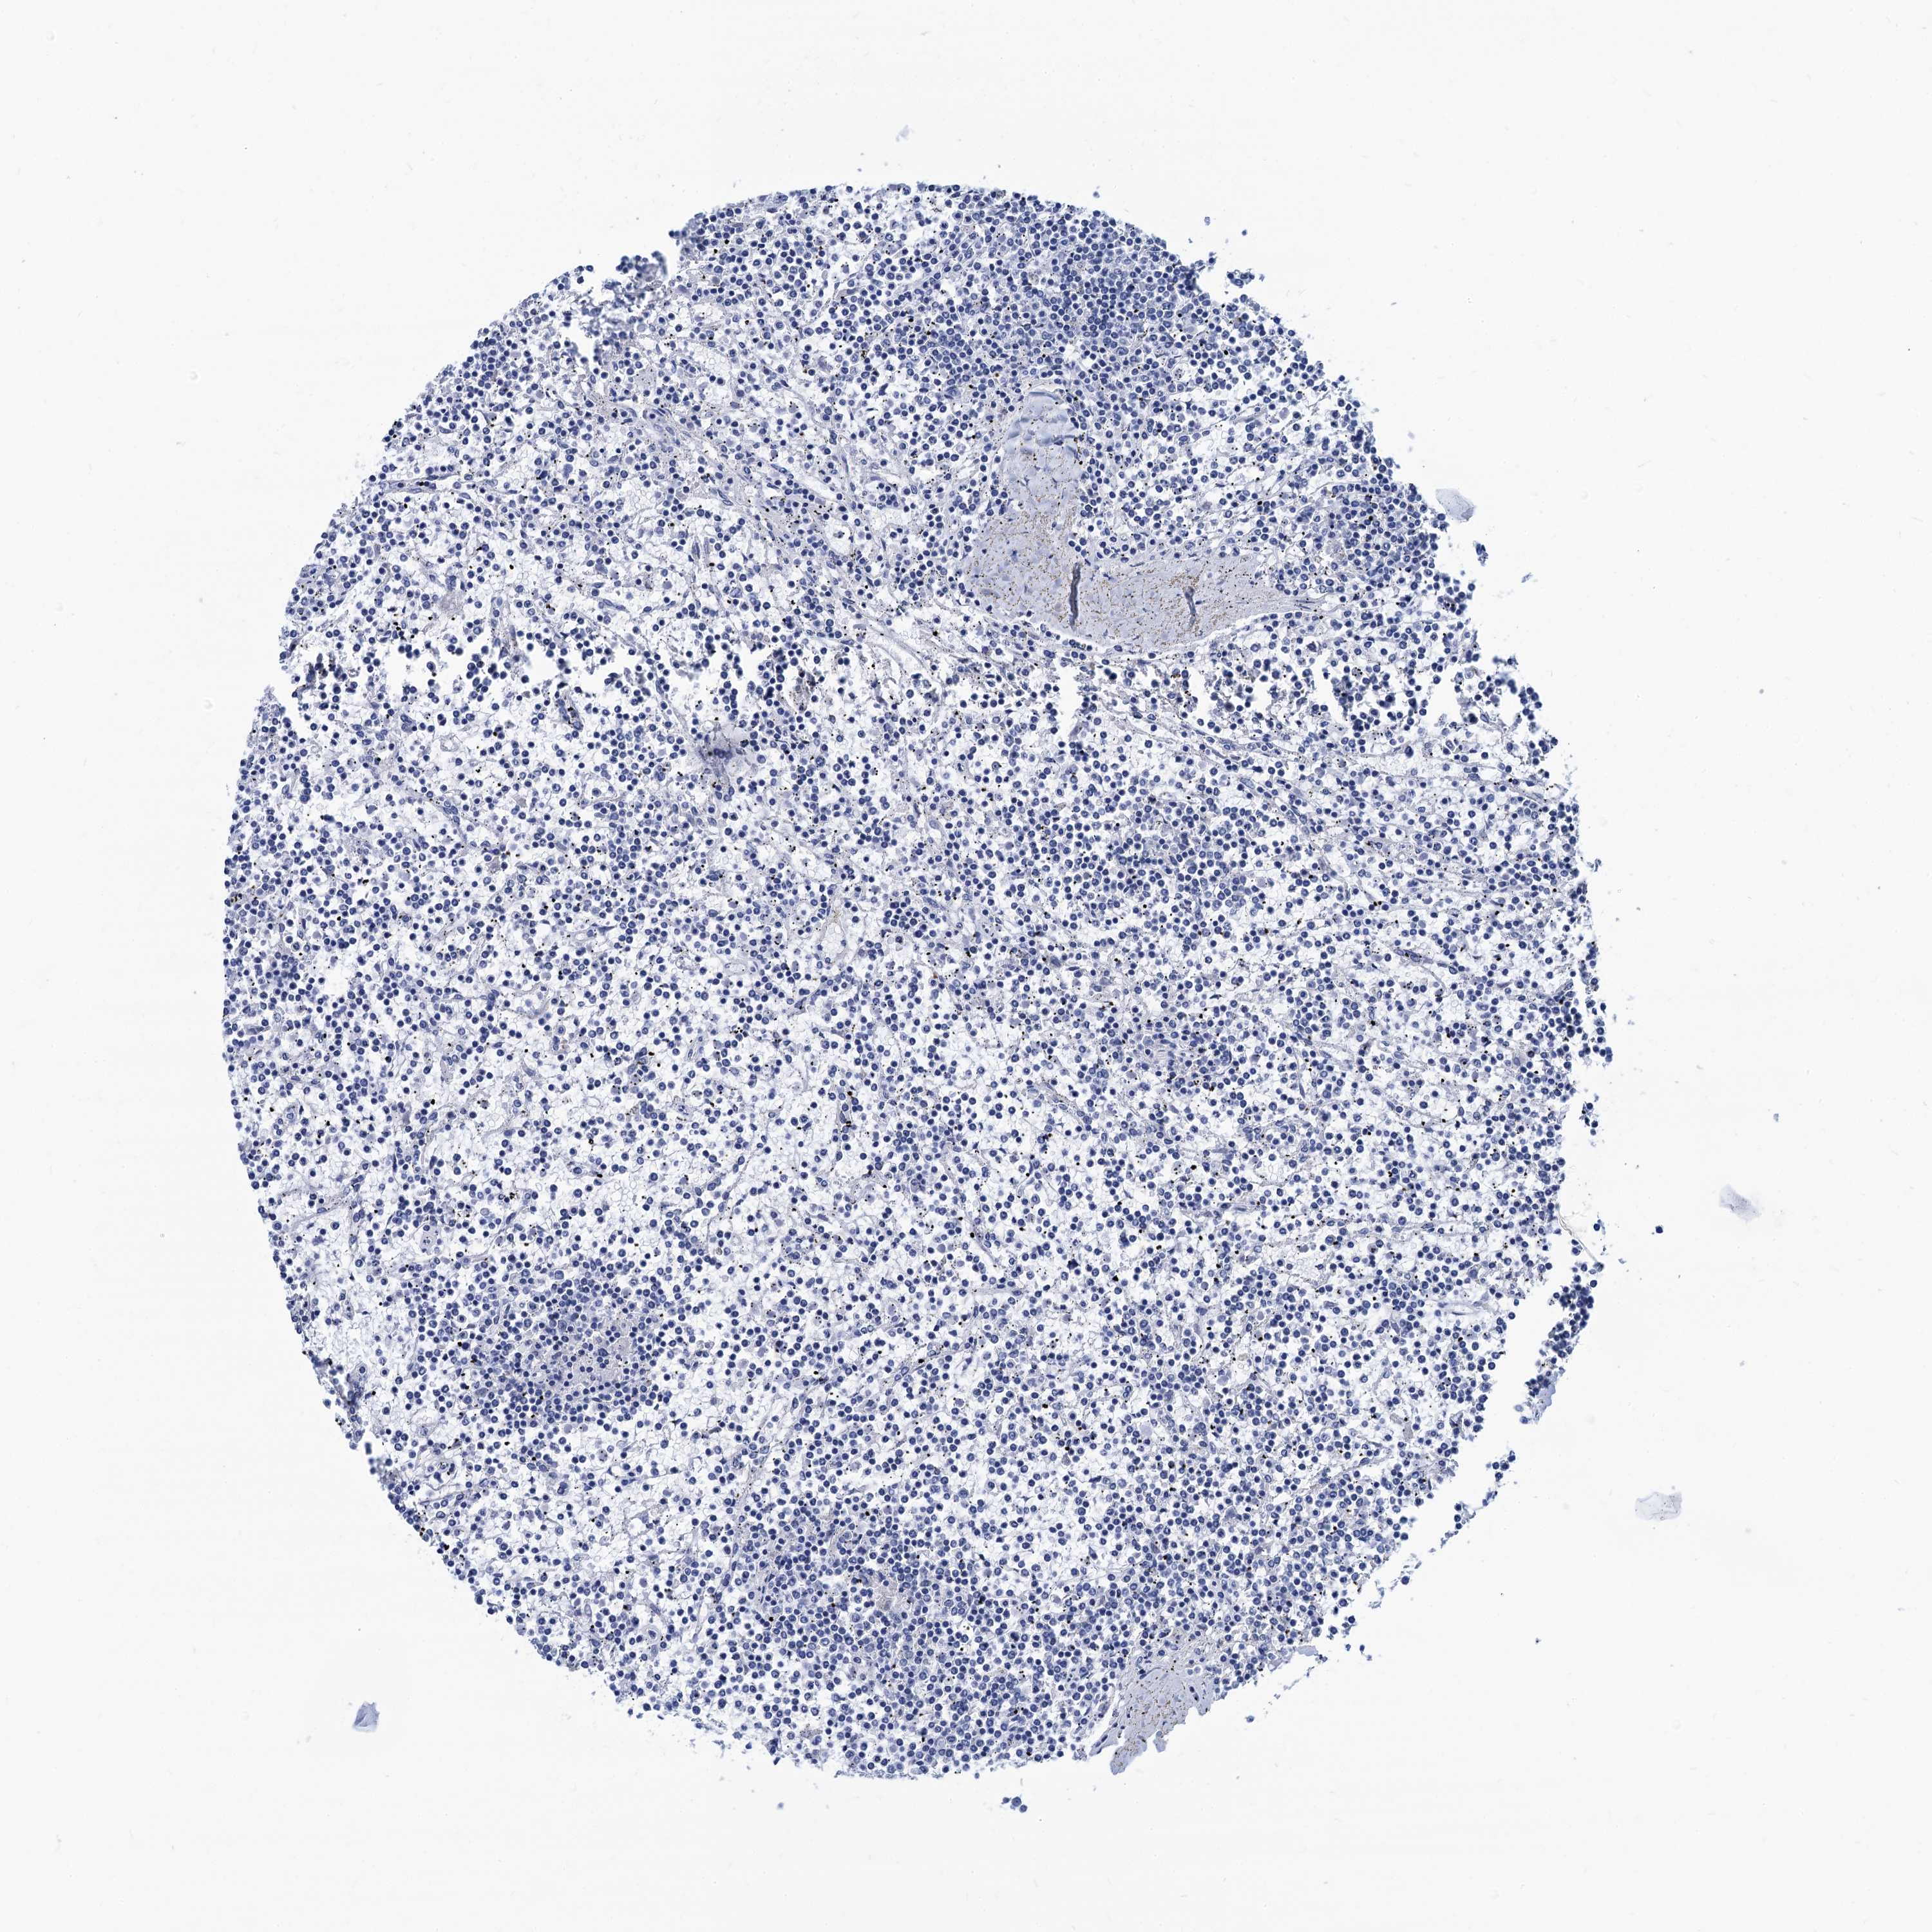

CANCER LYMPHOMA Show tissue menu

LYMPHOMA - Protein expressioni

A mouse-over function shows sample information and annotation data. Click on an image to view it in a full screen mode. Samples can be filtered based on level of antibody staining by selecting one or several of the following categories: high, medium, low and not detected. The assay and annotation is described here.

Each image is clickable and will lead to virtual microscopy that enables deeper exploration of all samples and also displays staining intensity scores, fraction scores and subcellular localization as well as patient and tissue information for each sample.

Antibody HPA040703

Hodgkin's disease, NOS

Malignant lymphoma, non-Hodgkin's type, High grade

Malignant lymphoma, non-Hodgkin's type, Low grade